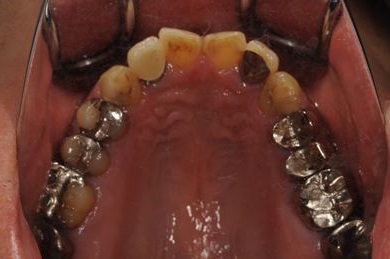

| 性別/年齢 | 男性 / 36歳 | ||||||||||||||||||||||||||||||||

| 主訴 | 義歯・インプラントの相談。 | ||||||||||||||||||||||||||||||||

| 治療方針 | 抜歯と同時にインプラント埋入を行い、治療期間を短縮する。 | ||||||||||||||||||||||||||||||||

| 治療内容 | インプラント4本(抜歯即日スピードインプラント)、メタルボンドセラミッククラウン4本 | ||||||||||||||||||||||||||||||||